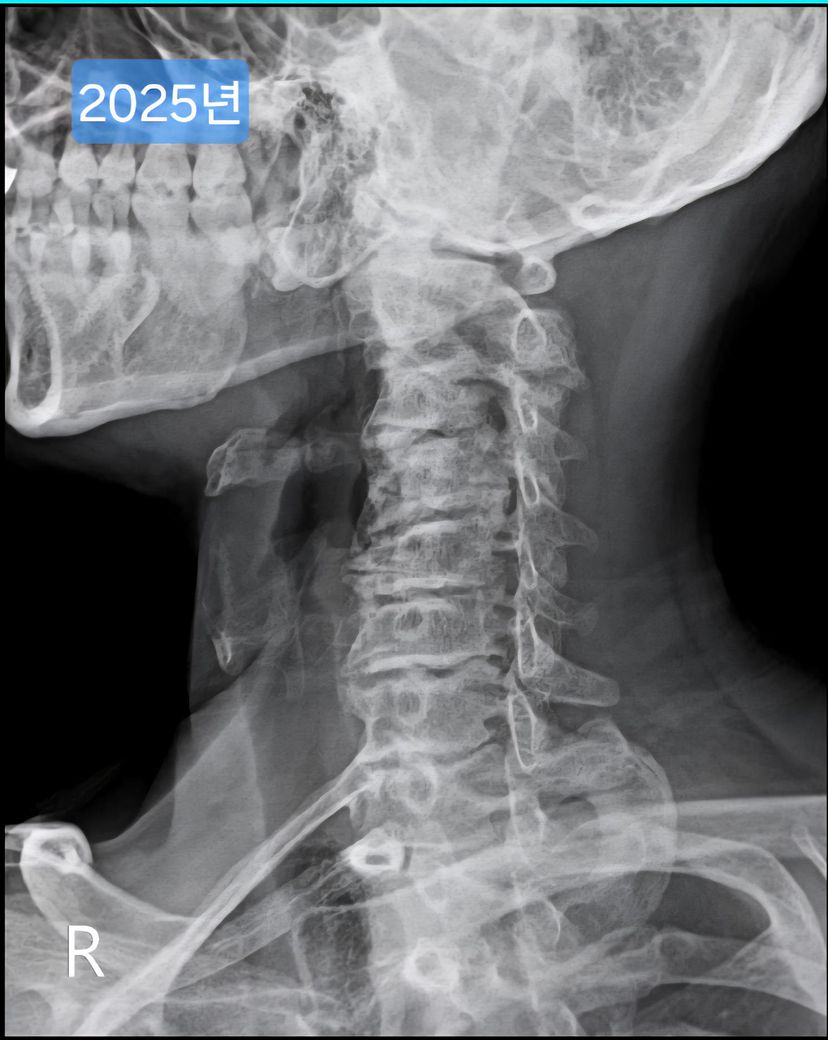

목 엑스레이 사진입니다. 많이 심각한걸까요?

오늘 찍은 2025년도 엑스레이와 9년전 사진을 업로드 해 드리겠습니다.

(이미지에 좌측상단에 해당연도 표시했습니다.)

1. 2016년과 2025년도 목이 상태가 많이 변했나요?

제가 보기엔 9년전에도 경추사이 간격이나 일자목이나 비슷한듯 보여서요.

->우선 사진상으로 봤을 땐 과거에도 충분히 경추 사이의 간격이 좁고, 목의 커브는 C자의 만곡 보단 일자목과 비슷해보이며 시간이 지나면서 누구나 겪는 퇴행성의 과정으로 보여집니다.

9년 전과 비교했을 때 경추 간격과 일자목 형태가 크게 달라진 것 같지 않아 상태가 오래 유지 된 것으로 보입니다. 오랫동안 비슷한 형태라면 큰 통증이나 신경 증상이 없다면 생활에 지장을 주지 않는 범위일 수 있습니다.

진료보신 선생님이 말씀하신 것 처럼 엑스레이 사진은 많이 안좋습니다. 단순 엑스레이만으로는 알 수 있는 부분들이 적기 때문에 통증이 지속된다면 MRI 촬영 등 추가 검사 필요하겠으며, 말씀하신 것 처럼 낮은 베개 사용하는게 좋습니다.